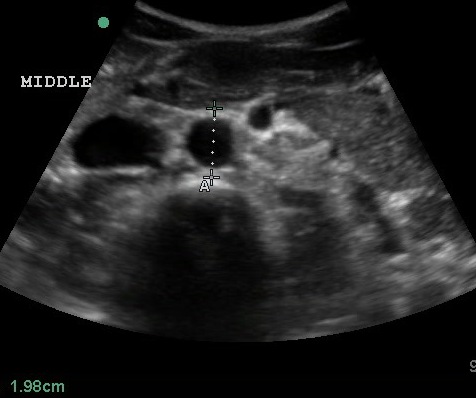

- Mid measurements should be obtained below the SMA branch point.

- Figure 4. Transverse view of the mid aorta